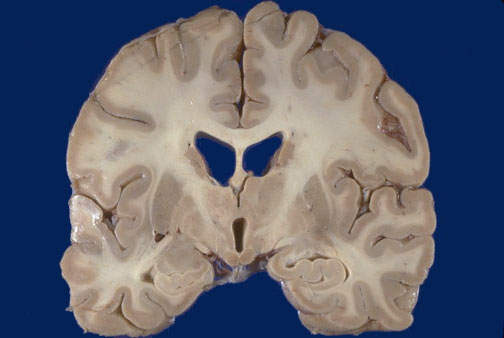

Identify the following regions of the normal brain in the image above: Corpus Callosum - Body of Caudate - Putamen - Globus Pallidus - Internal Capsule - Thalamus - Hippocampus - Mammillary Bodies - Lateral ventricle